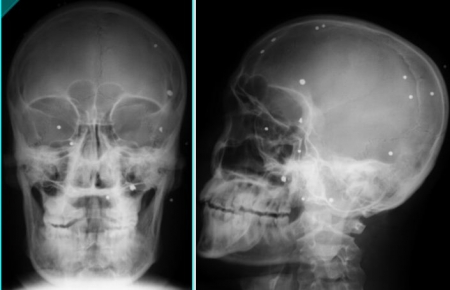

রেডিওগ্রাফিঃ নিজ

শুক্রবার ঘড়িতে সময় ০২ঃ০০ টা বায়তুল মোকারম জামে মসজিদ এ জুমা নামাজ শেষ করে আন্দোলনে নেমে যায় এই ভাই টি। হঠাৎ করেই তার সামনে এসে পড়ে তার ঈমাম এর রক্তাক্ত দেহ। রক্ত দেখে সে দৌড়ে বা পালিয়ে যায় নি সে ভাবে আমার সামনে আমার হুজুর আহত হয়েছে আমার বেচে থেকে কি লাভ। যেই ভাবনা সেই কাজ নেমে পড়ে সেও পাল্টা আক্রমন এ। সাবার আক্রমন দমাতে প্রসাশন এলোপাতাড়ি গুলি ছুড়তে থাকে। এবং কি সেও এক পর্যায় এ আহত হয়। তার সহপাঠিরা আহত দের ধর্মীয় চেতনা থেকে ইসলামি ব্যাংক হাসপাতালে নিয়ে যায়। বাংলাদেশ ইসলামি ব্যাংক হাসপাতাল তাদের কোন পরীক্ষা না করেই মাথা টিপে টিপে মিথ্যে শান্তনা দেয় এই বলে যে, মাথায় কোন প্রকার সমস্যা হয় নি এবং কোন ফরেন বডি নেই।(আহত লোকটির মাথাটিই উপরের ছবিতে) এবং রিলিজ করে কোন কাগজ না দিয়েই ঢাকা মেডিকেল কলেজ হাসপাতাল এ ভর্তি হওয়ার পরামর্শ দিয়ে অতি দ্রুত আহত হুজুর দের প্রস্থান করে।

দুই দিন পর লোকটি তার নিজ জেলা হবিগঞ্জ সাহিদ চক্ষু হাসপাতালে ভর্তি হয়। চোখে গুরুতর জখম থাকার কারনে ডাক্তার তাকে অরবিট হাড়ের একটি এক্স রে দেয়। রোগীটিকে দেখে আমার খুব মায়া হয় এবং আমি খুব যত্ন সহকারে পরিক্ষাটি করি। রিডারে ক্যাসেট দিয়ে আমি স্কিনে চোখ রাখতেই দেখি স্পিন্টার এর অবস্থান। আমি রোগীটিকে আমার কাছে নিয়ে আসলাম এবং তার মাথার ভেতরে অংশটুকু দেখালাম নিশ্চিত করলাম স্পিন্টার অবস্থান। এবং রোগীকে বললাম শেষ পর্যন্ত বাংলাদেশ ইসলামি ব্যাংক হাসপাতাল ও আপনার সাথে ষড়যন্ত্র করলো তাই না।